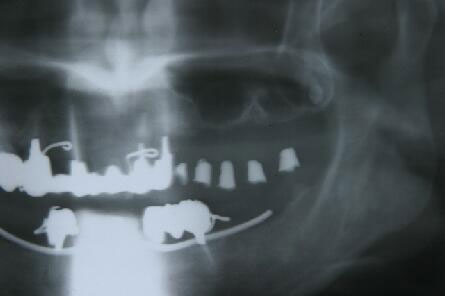

4ヵ月後に最終かぶせ物をしてメンテナンスへ

4ヶ月して、当初1〜3ミリしか存在しなっかた骨が7〜12ミリ程度(部位によって違う)になり 予定通り最終かぶせ物(メタルボンドポーセレン)を装着

左上(写真では右の上となります)に最終かぶせ物(メタルボンドポーセレン)を装着

8ヵ月後のエックス線写真